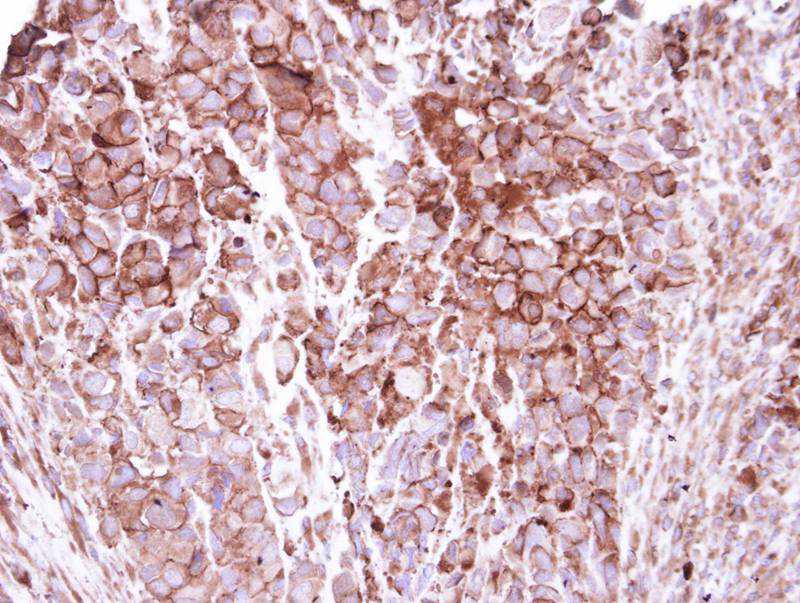

Immunohistochemical analysis of paraffin-embedded H661 xenograft, using ZO-1 antibody at 1: 250 dilution.